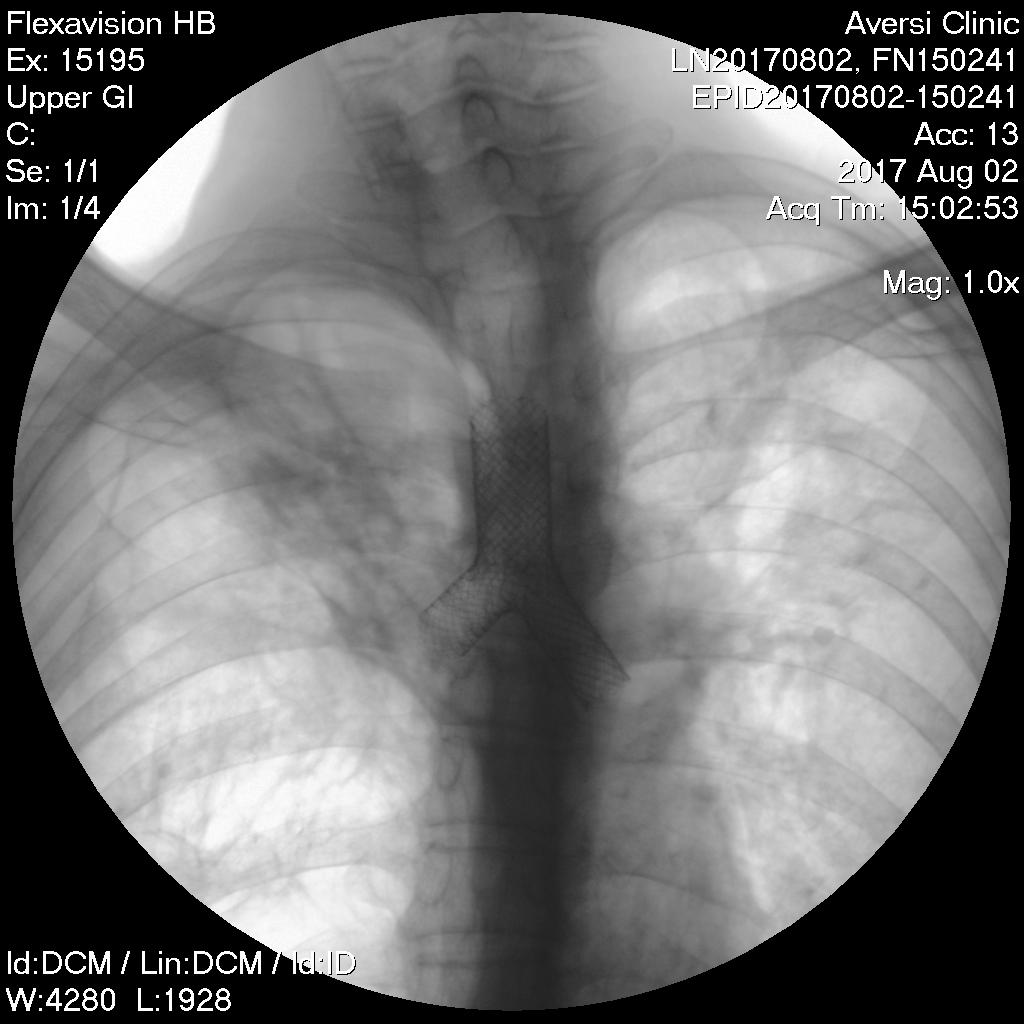

49 years old patient on 2007 was treated with anti TB chemotherapy due to pulmonary TB. On 2015 was relapse. During many years the patient has dyspnea, increased breathing failure, why he often was hospitalised. Spirometry showed severe obstruction of airways. CT scan revealed severe fibrosis of the upper lobe of the right lung, giant emphysematous bullas in the lower lobe. Narrowing lumen of the left main bronchus less then 3 mm. Bronchoscopy showed cicatricial stenosis of the left main bronchus. Patient’s condition was gettig worse. Because of suffocation he often was forced to call an ambulance. It was decided to perform tracheobronchial stenting as the only way out. Under the general anesthesia, using the rigid bronchoscope and radiological control, was inserted self expandable tracheobronchial stent (M.D.-18mm;T.L.-40mm;L-14mmX25mm;R-14mmX25mm). After stenting the patient’s condition improved significantly. 1 month after procedure patient feels well.

- Stenting

- After Stenting

- CXR After Stenting